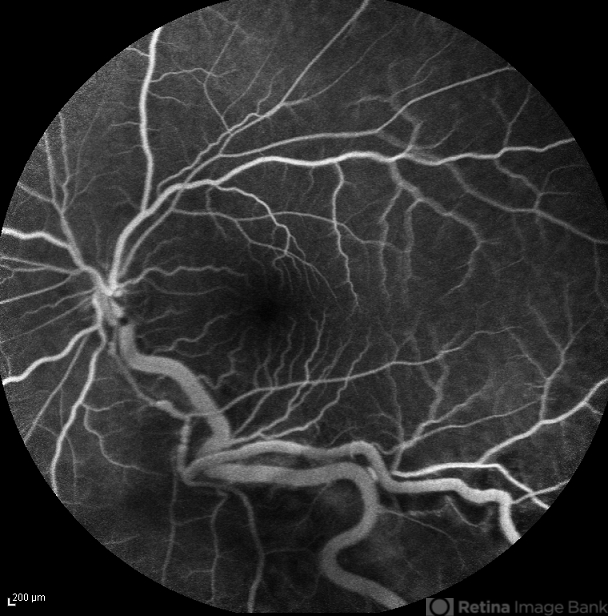

- Von Hippel-Lindau

- Mid venous phase FA image of the left eye of a 30-year-old woman with Von Hippel-Lindau. The afferent and efferent vessels have been filled.